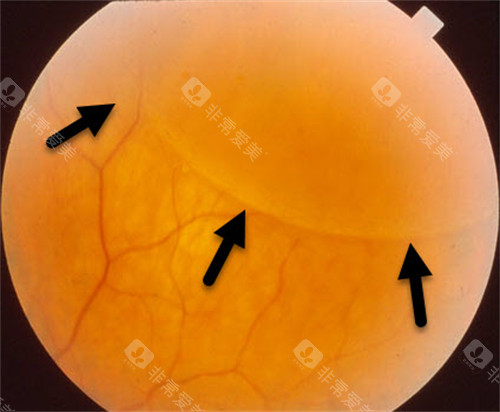

糖尿病视网膜病变,也被称为糖尿病性视网膜病变或糖网病。它是由于糖尿病导致视网膜微血管受损,进而影响视力。

随着病情的发展,患者可能出现视力下降、视物模糊、眼前黑影等症状,重度时甚至会导致失明,给患者的生活和工作带来极大不便。